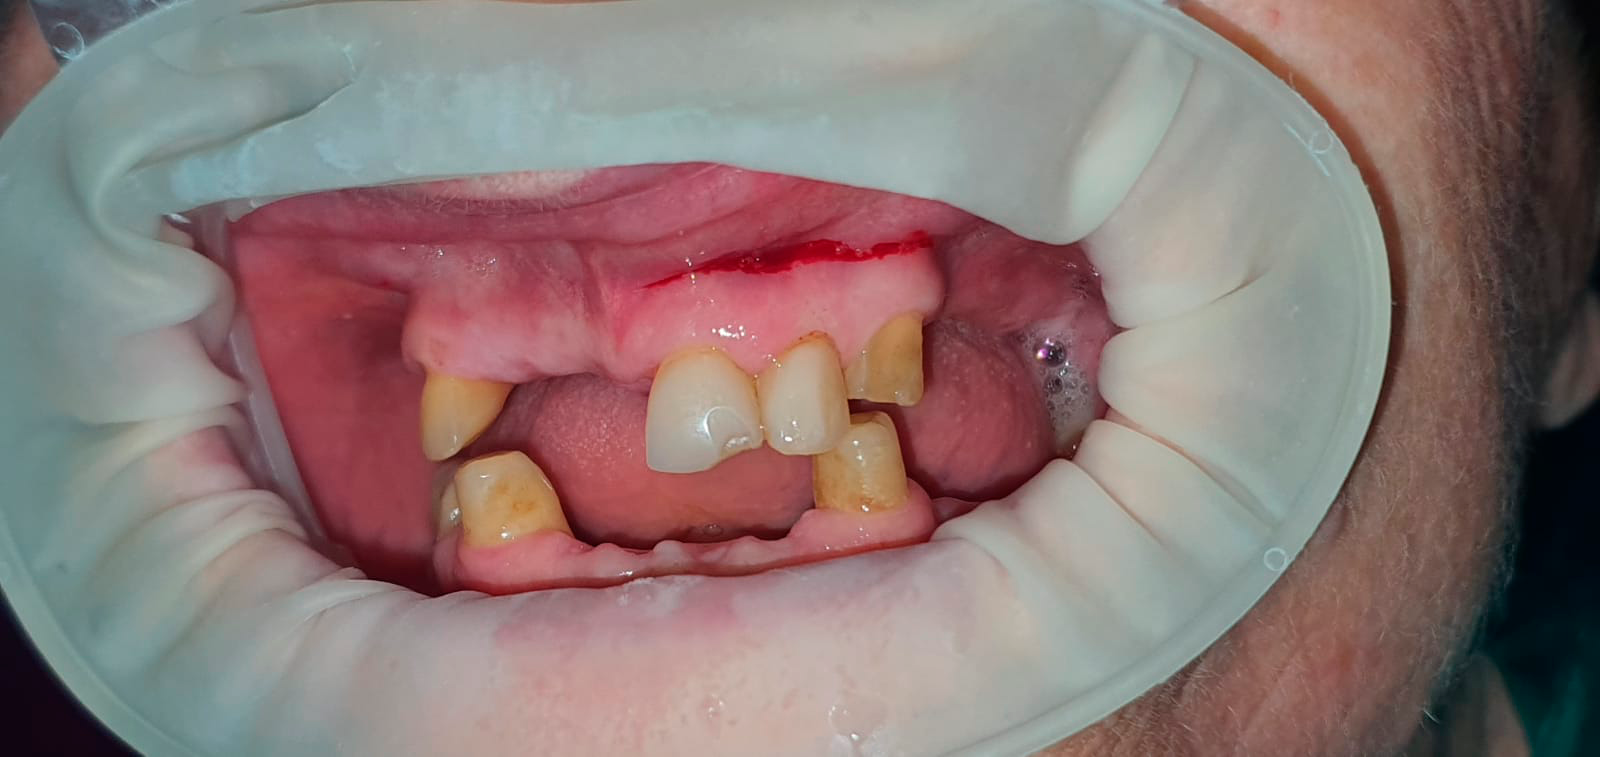

Реабилитация верхней челюсти циркониевыми коронками на имплантатах. Выполнил врач Краснов Д.А.

До